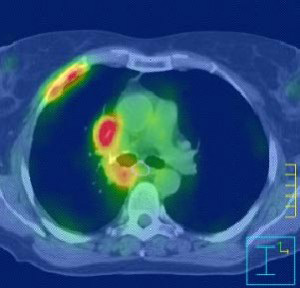

Η ακτινοχειρουργική με CyberKnife αντιπροσωπεύει μία πανίσχυρη και μεγάλης ακρίβειας τεχνική για ασθενείς με αρχική, υποτροπή ή μεταστατική εντόπιση όγκου στον πνεύμονα. Η θεραπεία είναι ασφαλής να δοθεί σε ασθενείς που δεν μπορούν λόγω άλλων παθολογικών καταστάσεων να χειρουργηθούν και προσφέρει μία πολύ καλή θεραπευτική επιλογή σε ασθενείς με υποτροπιάζουσα ή εμμένουσα νόσο που πριν είχαν ελάχιστες αν όχι καμία, δραστική θεραπεία ικανή να τους βοηθήσει.

Το CyberKnife είναι ένα σύστημα ακτινοθεραπείας που αποτελείται από ένα γραμμικό επιταχυντή τοποθετημένο επάνω σε έναν ρομποτικό βραχίονα.

Το CyberKnife είναι ένα σύστημα ακτινοθεραπείας που αποτελείται από ένα γραμμικό επιταχυντή τοποθετημένο επάνω σε έναν ρομποτικό βραχίονα.